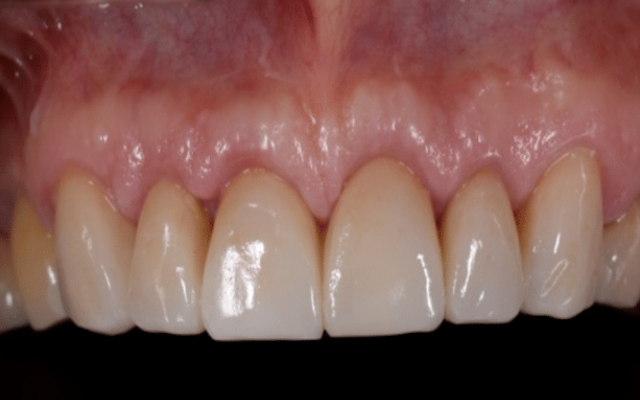

Crown lengthening can also be carried out for cosmetic reasons to expose more tooth structure to improve the appearance of the teeth or to reposition the gum tissues to an aesthetically acceptable position. This is a procedure that is often required where a patient has a “gummy smile” to reduce the amount of gum that is showing (Figure 9D, 9E and 9F).

Following crown lengthening, the gum has been repositioned to expose enough tooth structure for restoration with crowns.

The teeth have now been restored with long lasting crowns.